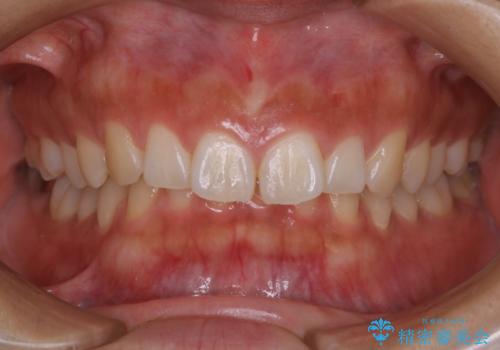

矯正治療前にホワイトニング

- 矯正治療前にホワイトニングがしたいとのことで来院されました。

処置前クリーニングとオフィスホワイトニングのエクセレントコースを行いました。

処置前クリーニングとオフィスホワイトニングのエクセレントコースを1回行いました。

この患者様は、歯科矯正に1、2年かかり矯正中はホワイトニングをすることが出来ないため、歯を白くしてから矯正治療にすすみたいとのことでオフィスホワイトニングを行いました。1回の施術で2.3トーン白くなり、とても白くなりました。ホワイトニングは何度も重ねて白くしていくのですが、1度で満足のいく色見になったため一旦様子を見ることにしました。

1ヶ月後来院して頂きチェックしたところ、やはり後戻りがあったため、再度オフィスホワイトニングを行うことになりました。

1回のオフィスホワイトニングですとこのくらいの後戻りがあるため、ホワイトニングを考えている方は是非参考にしてください。